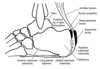

haglund’s radiographic angle

- (1) Fowler And Philip Angle > 75° (65°)

- (2) calcaneal inclination

- (3)Total Angle > 90° - Ruch

- Parallel Pitch Lines - Pavlov (pictured below) nothing should project above